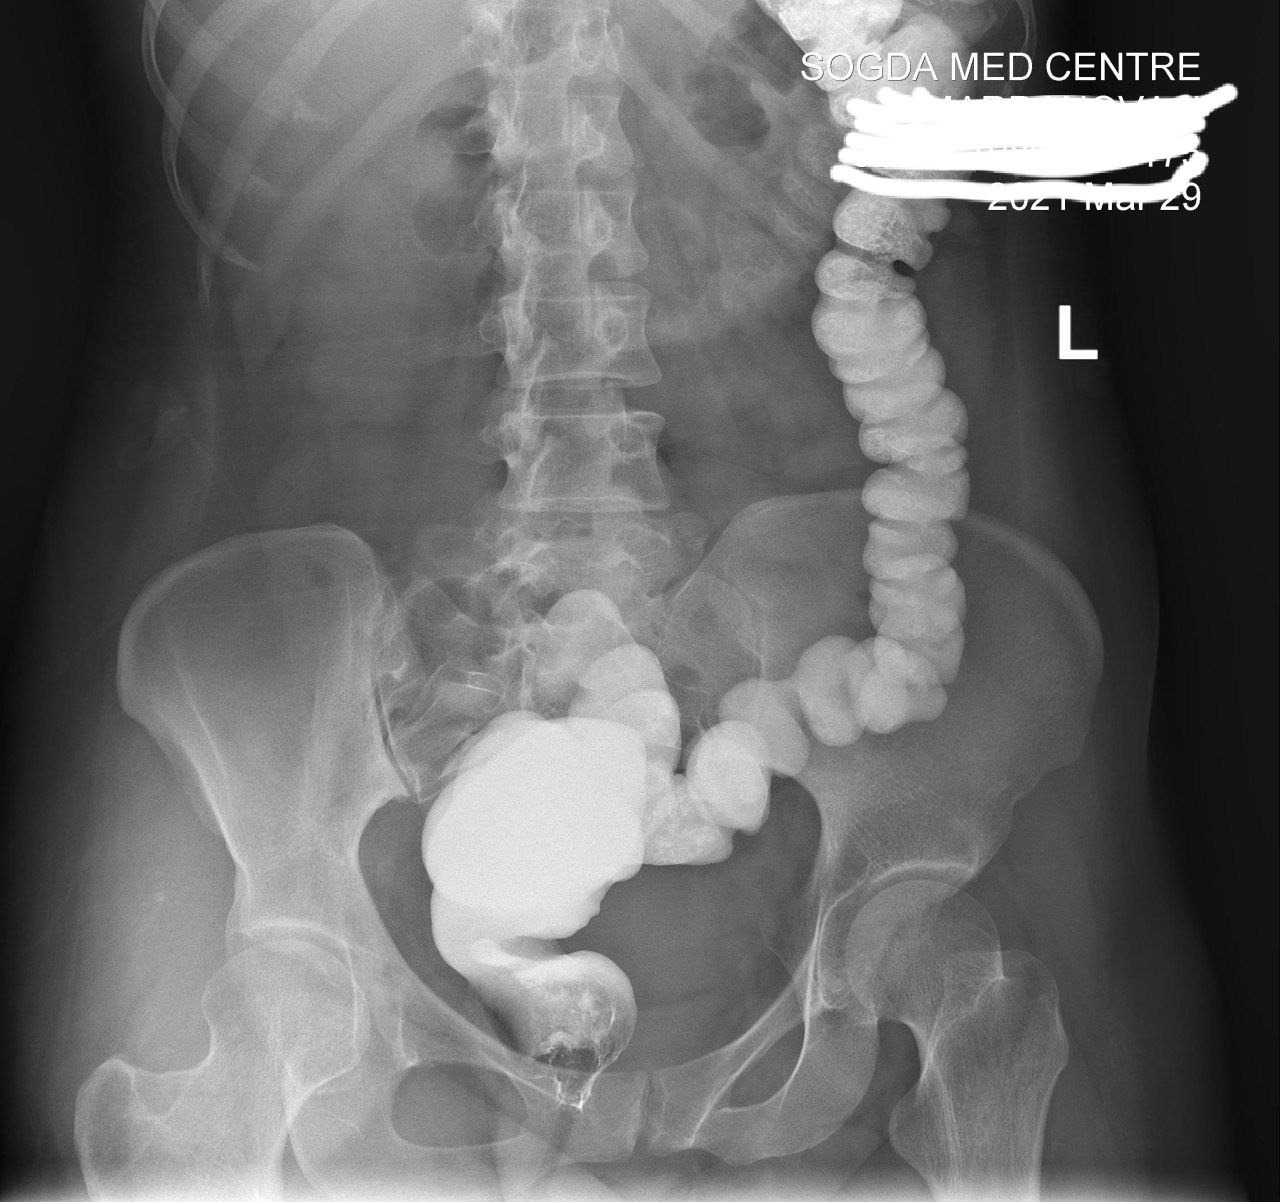

Ирига уже другая поциентка безпокоит запор

Долихосигма . Хронический колит

Нет ни того ,ни признаков другого

На таких исследованиях обычно ищут органическую патологию, а не всякую ерунду. Раз Вы утверждает ,что здесь какой то колит, то каковы его признаки?

Есть признаки долихи и колита

Потому что зделали колоноскапию 100% подтвердил